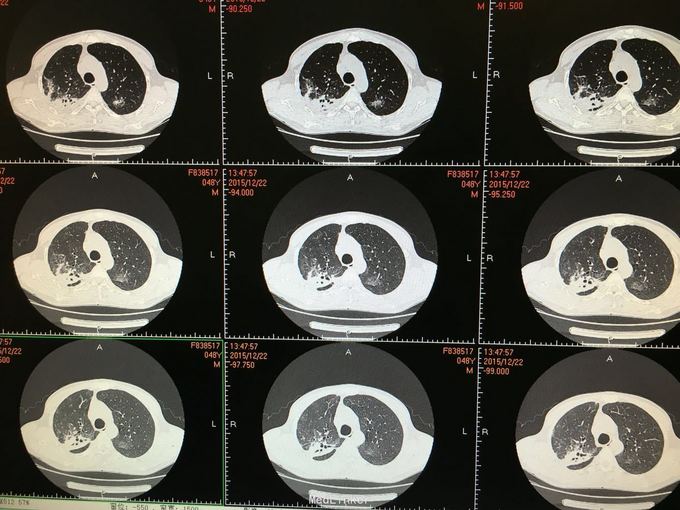

间断咳嗽咳痰5月余。患者缘于半年前确诊为骨髓增生异常综合征,并行造血干细胞移植术。术后出现发热,完善相关检查考虑为肺部真菌感染,给予抗感染治疗后体温正常,病情好转出院。出院后仍有间断咳嗽咳痰,咳黄色痰,无发热,自行口服伏立康唑200mg,2/日治疗,12月初复查CT提示双肺病灶较前进展,右肺中叶新增病灶。

根据症状体征及辅助检查,结合病史考虑真菌感染可能性大。进一步气管镜检查,结果如下。组织活检标本可见。病理回报提示真菌团,培养见曲霉菌生长。明确诊断后给予两性霉素B雾化吸入及伏立康唑静脉应用抗真菌治疗,同时给予环孢素口服。

造血干细胞移植后肺部感染常见,其中以曲霉、卡肺等多见,患者经气管镜检查已将真菌团块取出。术后给予监护,口服云南白药、垂体后叶素雾化止血等治疗,无明显出血,症状逐渐好转。复查CT也明显好转。